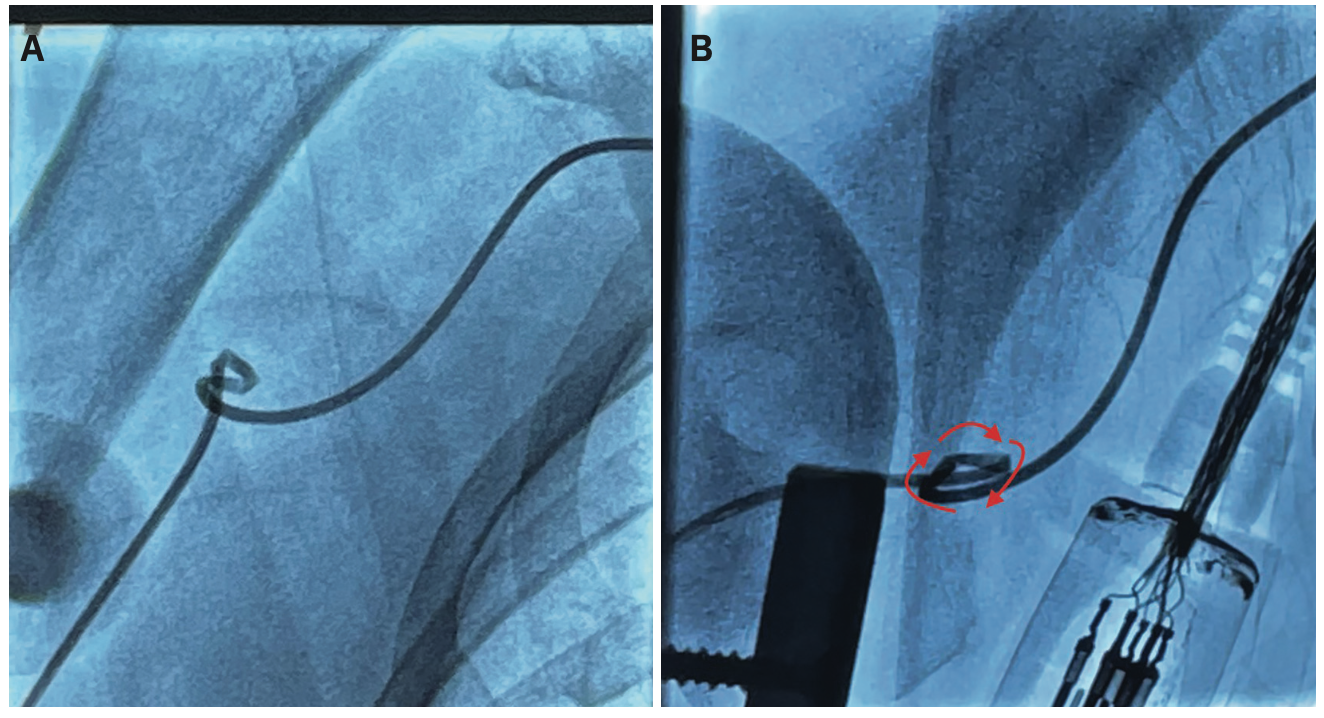

After access into the RRA, a 5 French Tiger Catheter (Terumo) was passed into the AA with moderate ease; however, the catheter crossed the trachea under fluoroscopy, noted immediately. This offered an indication of tortuosity aside from underlying clinical factors (age +65, hypertensive, short stature). Prior to engaging the coronaries, with the catheter sitting just at the sinotubular junction, we took a quick “flouro store” of the tortuosity in left anterior oblique/caudal views in order to adequately delineate the tortuosity and document it for any subsequent catheterizations. We found a tight subclavian loop (Figure 1) that proved to be problematic for the procedure. After several minutes of catheter manipulation, no further torque was being transmitted to the tip of the catheter and contrast was unable to be injected, with an altered aortic pressure waveform. We scanned the catheter through the upper vasculature and found the catheter was kinked in the distal right subclavian. A standard J-wire was introduced into the catheter to attempt to straighten the kink, to no avail. After further manipulation trying to unravel the kink, it moved into the mid brachial artery (Figure 2A-B). A hydrophilic Glidewire (Terumo) was then utilized, with the same results. We thought a possible solution would be to obtain femoral access, snare the catheter from the distal tip, and unravel the catheter; however, with the patient being pre-TAVR with PVD, we sought to avoid femoral access unless all other options were exhausted. We also postulated the use of this technique from the left radial, but with the degree of tortuosity and the tip of the catheter sitting distally in the right subclavian, the attending physician thought it would be a monumental feat.